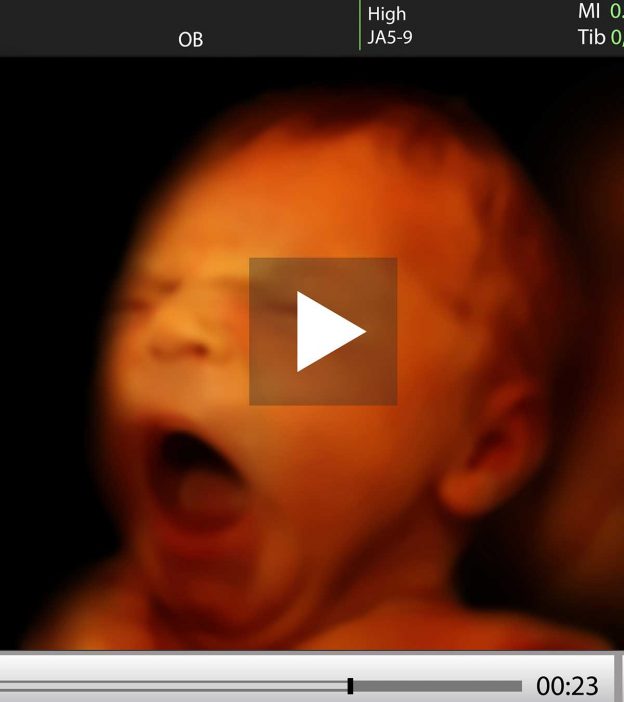

www.lupon.gov.ph4d Ultrasound - YouTube

www.lupon.gov.ph4d Ultrasound - YouTube

www.youtube.com4d ultrasound

www.youtube.com4d ultrasound